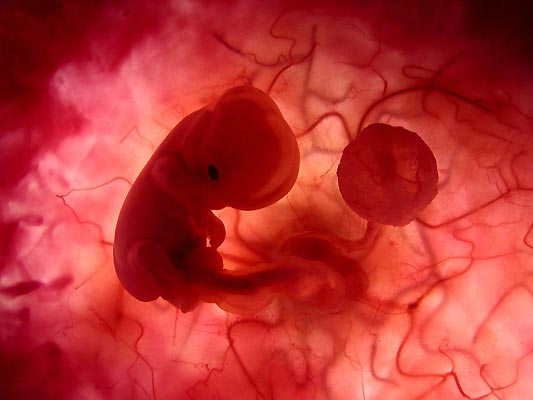

Primeras semanas. Aún no han aparecido los primeros rasgos humanos y, por su fisonomía, podría tratarse de cualquier mamífero.